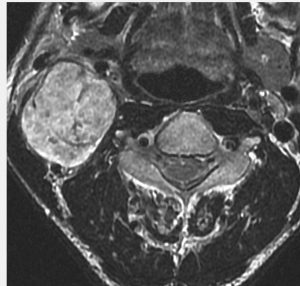

症例:気道狭窄を呈したもの:副咽頭間隙腫瘍 parapharyngeal tumor

頸静脈孔にも腫瘍があり頸部へ伸展した迷走神経鞘腫です。咳が出る,右下にして寝ると痰が詰まる,咽せるという症状で発症しました。摘出すると嚥下障害が出る可能性があるので,9年間経過観察しました。徐々に増大して,正中方向へ伸展して気道狭窄を生じました。睡眠時無呼吸,痰が詰まって苦しくなって夜中に目覚めてしまうという症状になりました。

内部から核出 enucleationしました。腫瘍周辺に迷走神経組織があるので,中心から内部の腫瘍だけを摘出減荷する方法です。左術前,右術後。